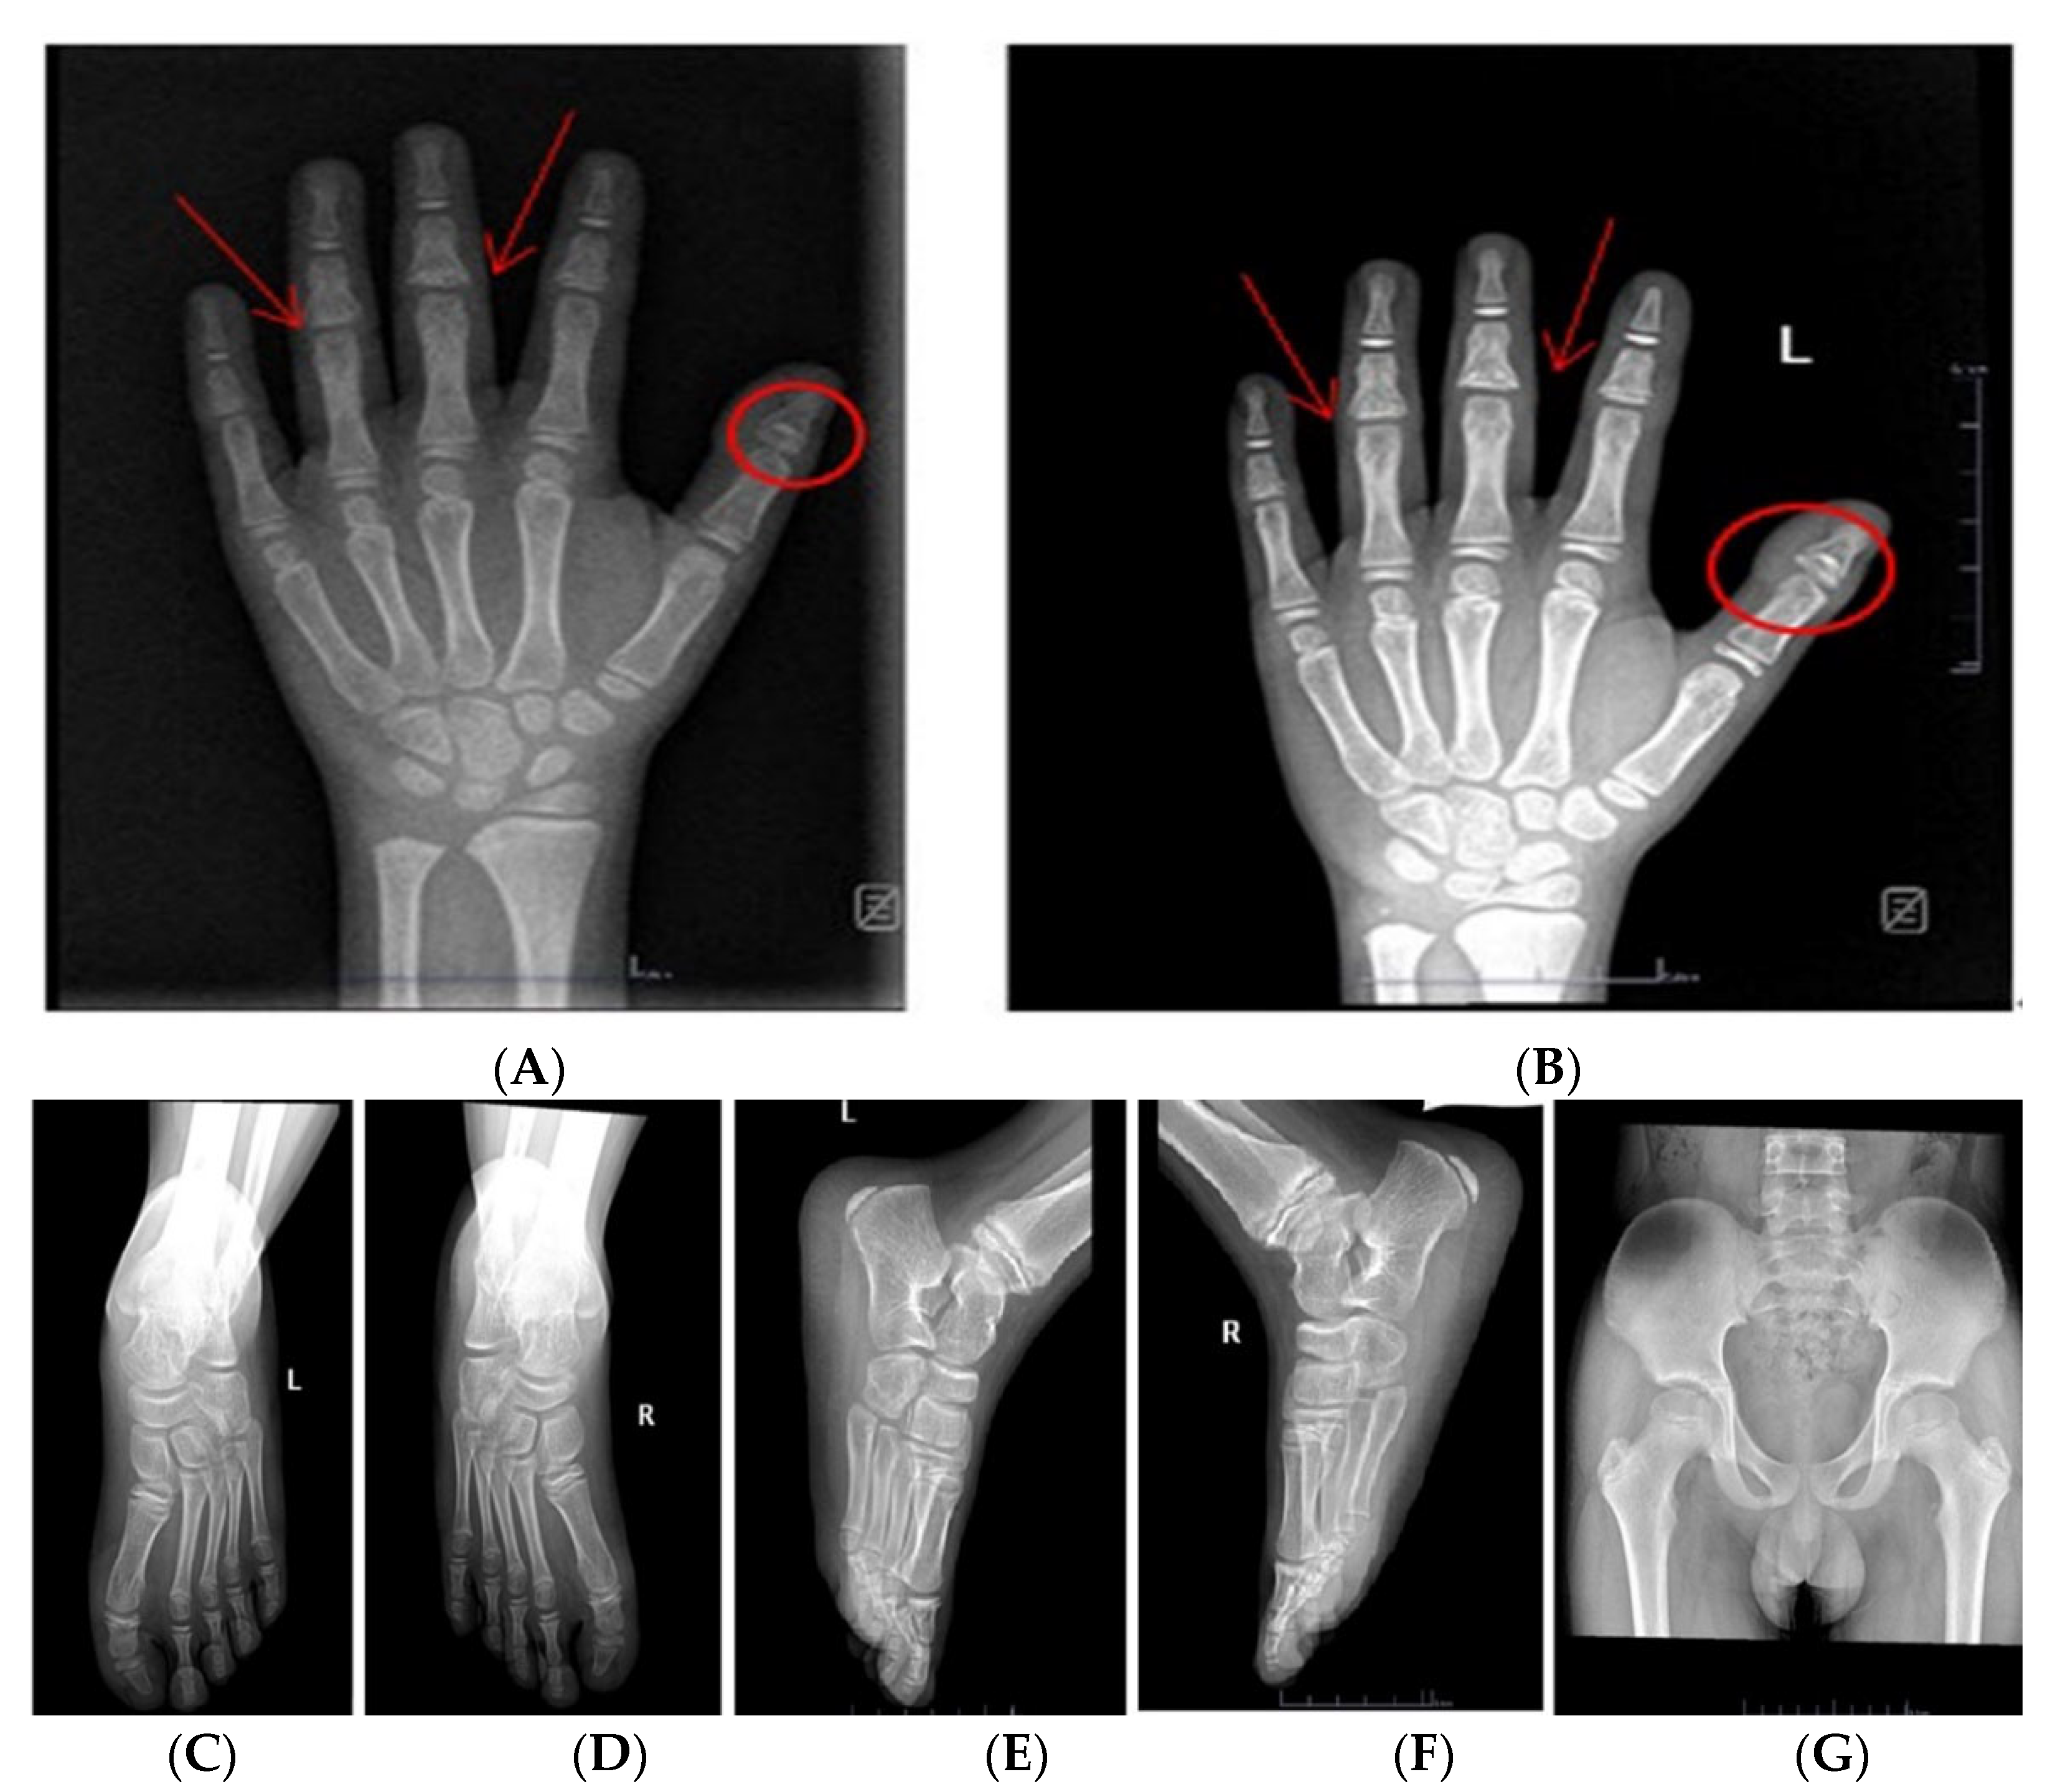

The radiograph of the left hands showed pollex phalanx epiphyses; particularly, the first proximal phalanges are characterized by cone-shaped epiphyses (circle) and are embedded with thickening of surrounding soft tissue; shortness of middle phalanges; and the middle phalanges of the third to fourth finger had a fusion of diaphysis and epiphysis. It also showed a bone age of about 9 years old according to the Greulich and Pyle method (Figure 2A). Furthermore, the anteroposterior and lateral views of the foot showed that the first, third, and fifth proximal phalanges of both feet were conical epiphyses (Figure 2C–F). The pelvis showed no obvious abnormal X-ray signs (Figure 2G). Testicular volume by ultrasound on the left was 3.54 mL and on the right was 3.24 mL. An MRI showed the normal size and location of the pituitary gland and stalk. No pathological abnormalities were found by heart, thyroid, and abdominal ultrasound.

Figure 2.

X-ray report of the child: Frontal radiographic findings of the left hands of the child: (A): The photograph of the hands shows brachydactylia with shortening of the middle phalanges of all fingers. The coned epiphyses of the first proximal phalanges (circles) and more subtle, partially fused coned epiphyses of the third to fourth middle phalanges (arrows) can be noticed. Bone age (9 years) was delayed compared to chronological age (11 years). (B): The radiograph of the left hand notes a chronological age of 11 years and 6 months. (C,D): Anteroposterior radiograph of the foot; (E,F): Lateral radiograph of the foot: Foot X-ray for him demonstrates that the 1st, 3rd, and 5th proximal phalanges of both feet were conical epiphyses. (G): Plain radiographs of the anteroposterior view of the pelvis: no obvious abnormal X-ray signs in the pelvis.